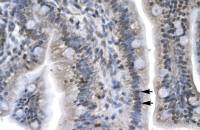

IHC-P analysis of human lung cancer (A), colon cancer (B), ovarian cancer (C) and mammary cancer(D) using GTX82992 N-Cadherin antibody [5D5].

IHC-P analysis of human Placenta tissue using GTX82992 N-Cadherin antibody [5D5].